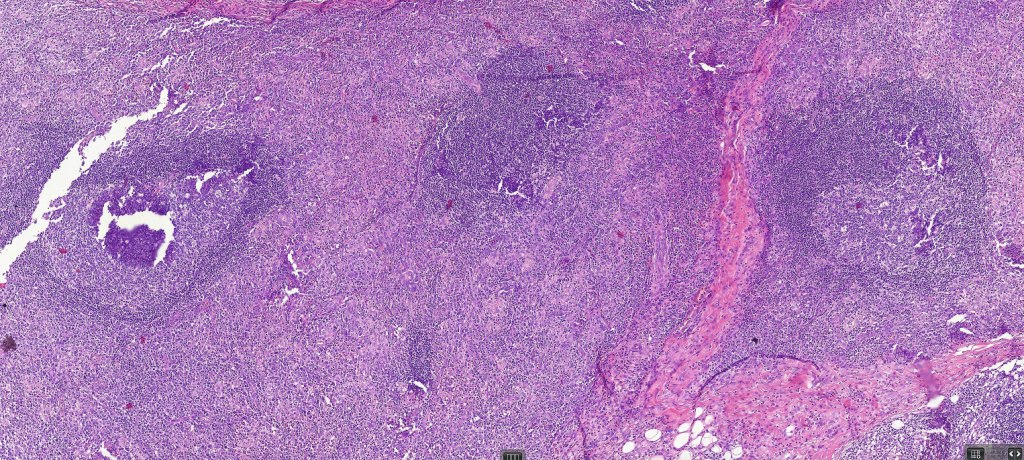

Histological features

•Epidermal involvement often absent

•Follicular infiltration by atypical lymphocytes & Sézary cells

•+/- mucinosis

•+/- basaloid follicular hyperplasia